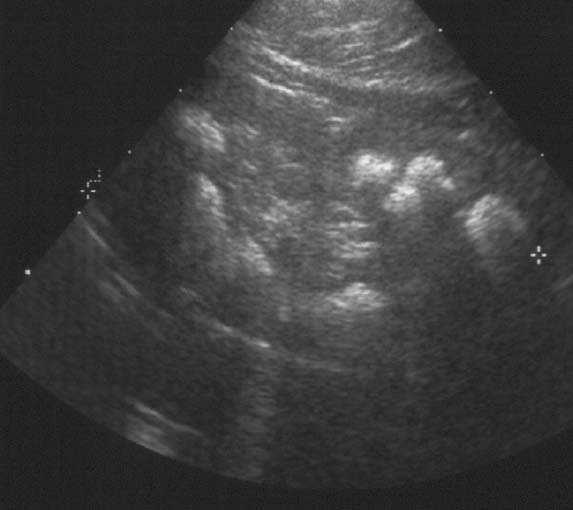

A 5-year-old girl was referred for further diagnostic work-up of rickets and bilateral nephrocalcinosis. She is the first child of healthy unrelated parents. She was born after an uneventful pregnancyat 40 weeks gestation, with a body weight of 2,680 g. Body height and weight remained below the 3rd percentile,she was reported to drink a lot, and psychomotor development was normal. When investigations were carried out for short stature,rickets and bilateral medullary nephrocalcinosis were observed by both U/S and X-ray. The girl has two sisters, aged3 years 6 months and 1 year 6 months, respectively, who are in good health to date. At presentation, body height was 96 cm and weight 13 kg. Blood pressure was 106/50 mmHg. Physical examinationwas normal except for large wrists, moderate genu valgum,and mild femoral bowing.Blood chemistry yielded the following information: urea (52 mg/dl) and creatinine (0.8 mg/dl), total calcium (10.7 mg/dl), magnesium(1.8 mEq/l), phosphate (1.6 mg/dl), and alkaline phosphatase (909 IU/l), parathyroid hormone (PTH) (<0.2 pg/ml) (normal 10–60) and 1,25-(OH)2 vitamin D (79 pg/ml) (normal 18–45). Serum electrolytes,albumin, transaminases, and uric acid were within normal ranges.Urine microscopy showed white cells but no erythrocytes. A24-h urine collection yielded 430 mg of protein per 1.73 m2 and 6.2 mg/kg calcium; excretion of uric acid, amino acids, and oxalate were normal and there was no glucosuria. Urinary β2 microglobulin/creatinine ratio was 1,312 μg/g. The maximal urinary osmolality was 304 mosmol/kg water under DDAVP stimulation. Bone X-rays showed metaphyseal lesionstypical for rickets (Fig. 1); bone age was 5 years. Renal U/S confirmed pronounced bilateral medullary nephrocalcinosis. The patient had been investigated at the age of 1 year because of poor weight gain. At that time, serum calcium was 12.1 mg/dl,phosphate was 3.9 mg/dl, and serum creatinine 0.6 mg/dl. She hadtaken vitamin D supplements (300 IU daily) up to the day of diagnosis.